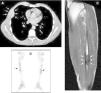

Tumores pardos pretibiales como manifestación inicial de un hiperparatiroidismo primario

Pretibial brown tumors as first manifestation of primary hyperparathyroidism